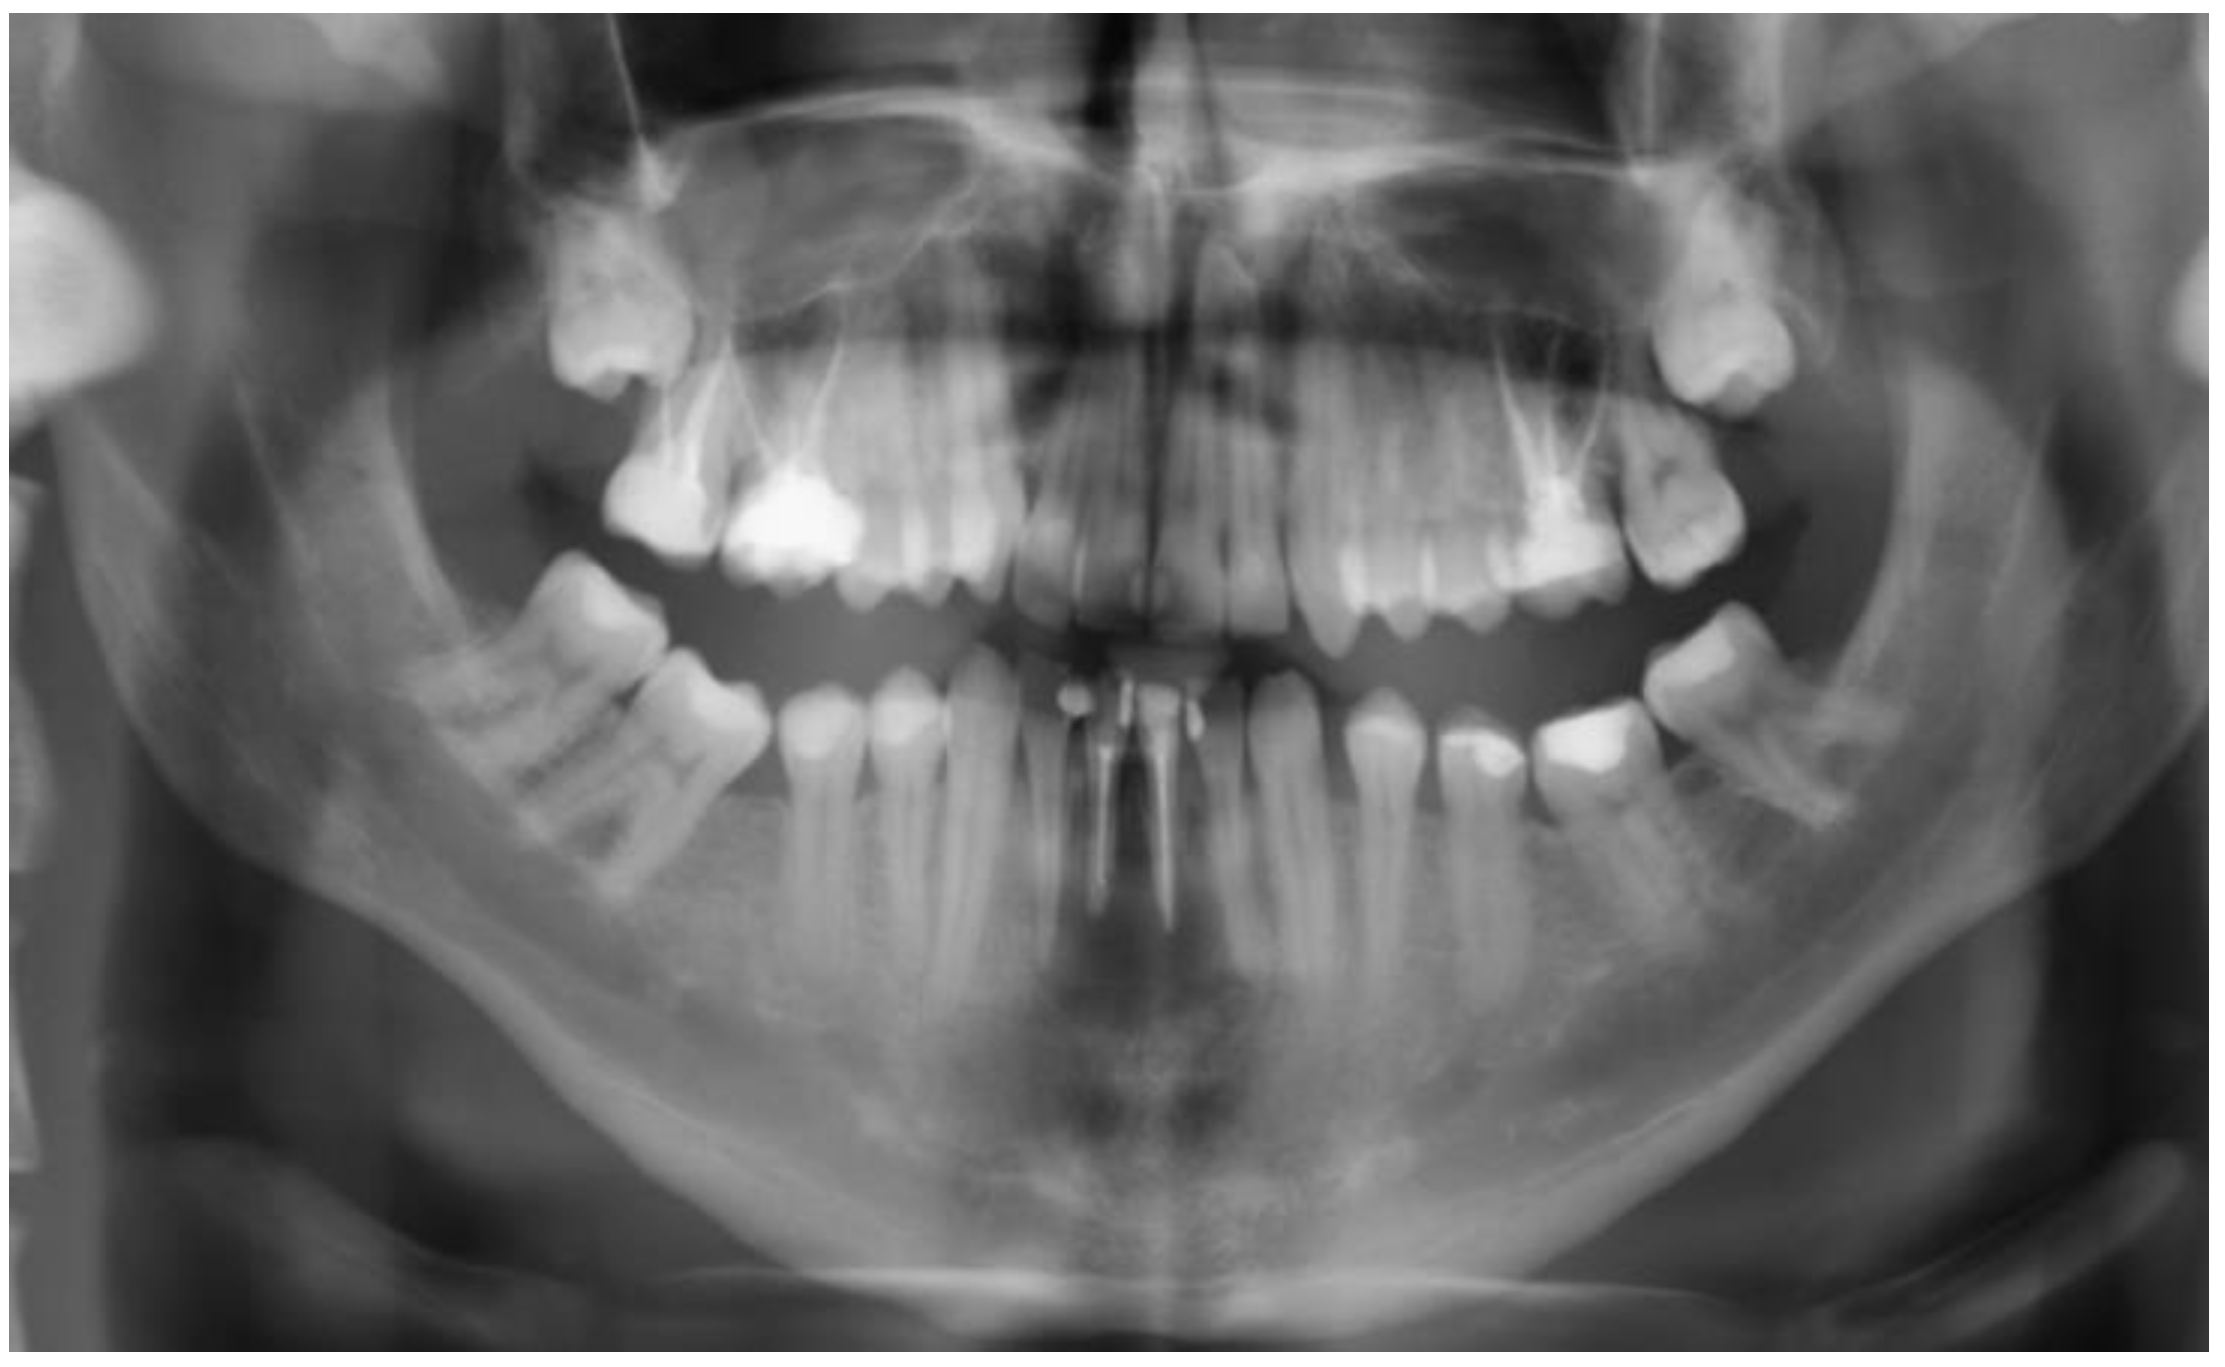

2. Case Description